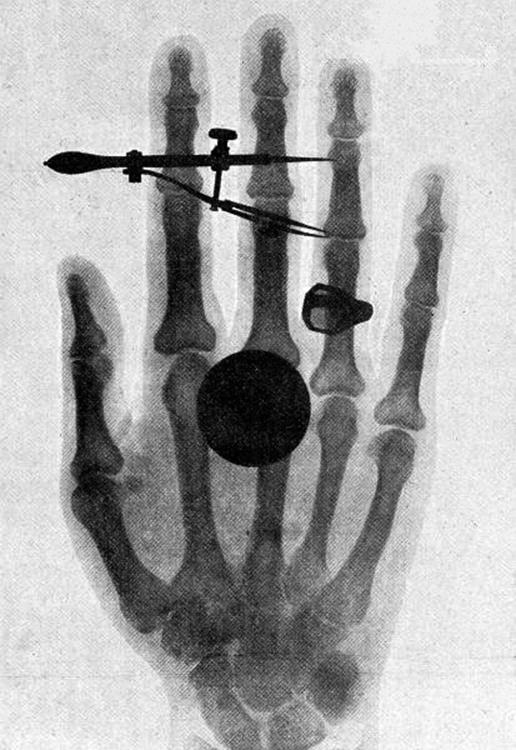

High photon energy also enables rays to penetrate materials, since a collision with a single atom or molecule is unlikely to absorb all the ray’s energy. This can make rays useful as a probe, and they are sometimes used in medical imaging. X-rays, as you can see in Figure 12.11, overlap with the low-frequency end of the ray range. Since X-rays have energies of keV and up, individual X-ray photons also can produce large amounts of ionization. At lower photon energies, X-rays are not as penetrating as rays and are slightly less hazardous. X-rays are ideal for medical imaging, their most common use, and a fact that was recognized immediately upon their discovery in 1895 by the German physicist W. C. Roentgen (1845–1923). (See Figure 12.12.) Within one year of their discovery, X-rays, which were once called Roentgen rays, were used for medical diagnostics. Roentgen received the 1901 Nobel Prize for the discovery of X-rays.